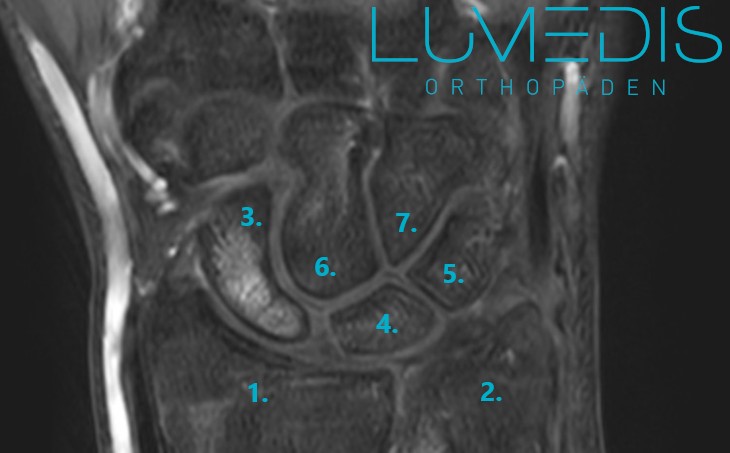

MRT einer Verletzung der Handwurzel (scapholunäre Dissoziation)

MRT eines Handgelenk mit Handwurzel mit Bandverletzung